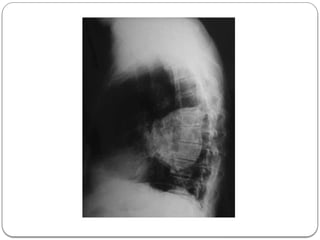

6. Posteroanterior chest X- ray (Figure 1) examination revealed a large left hilar

mass. In addition to a lack of aeration of the lower lobe of the left lung, there was

minimal costophrenic sinus bluntness

PHYSICAL EXAMINATION 1. VitalSign : BP: 140/80 mm Hg, PR: 90 beats/minute, RR: 16 breaths/minute, T.ax : 36°C 2. Cardiac and other system examinations were normal, but there was a decrease of breathe sounds in the left infrascapular area in the auscultation SUPPORTING EXAMINATION 3. CBC, biochemical and serological analyses were normal 4. Normal erythrocyte sedimentation rate of 10 mm/h and a white blood cell count of 9×109/L 5. High sensitivity C-reactive protein and serum D-dimer levels were found to be normal 6. Posteroanterior chest X- ray (Figure 1) examination revealed a large left hilar mass. In addition to a lack of aeration of the lower lobe of the left lung, there was minimal costophrenic sinus bluntness